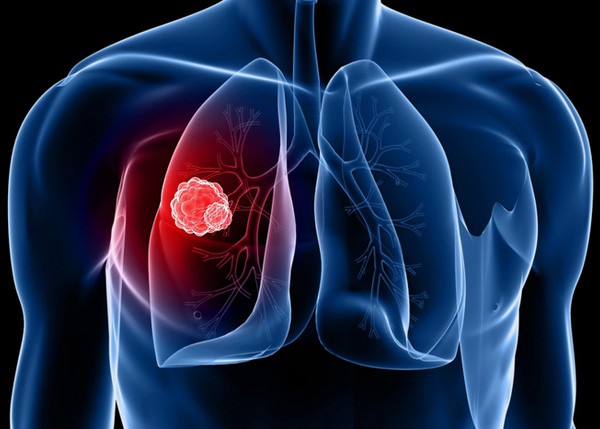

Theo Hiệp hội Phổi Hoa Kỳ, khoảng 230.000 người Mỹ được chẩn đoán mắc bệnh ung thư phổi hàng năm và đó là nguyên nhân hàng đầu gây tử vong do ung thư. Thông thường, những người hút thuốc hoặc công nhân làm ở khu công nghiệp có nguy cơ mắc bệnh cao nhất. Rachael không thuộc một trong 2 nhóm đó, nhưng cô lại không nhận ra là nguyên nhân gây bệnh lại ở chính trong căn nhà của cô. Đó là khí radon trong nhà. Radon là khí phóng xạ không mùi, thấm ra từ đất và có thể tích tụ trong một số ngôi nhà.

Nhiều người cho rằng, chỉ những người hút thuốc hay hít phải khói thuốc thụ động mới bị ung thư phổi. Thực tế, ung thư phổi có thể xuất hiện ở người không hút thuốc.

Ngoài thuốc lá, ung thư phổi dễ tìm đến bạn nếu bạn sống trong môi trường không khí và điều kiện sống bị ô nhiễm, có thể là từ hơi đốt ở gia đình, xí nghiệp, hơi xả ra từ các động cơ; khí radon - sản phẩm của sự phân hủy tự nhiên từ uranium trong đất, đá, nước và cuối cùng trở thành một phần của không khí mà chúng ta hít thở hàng ngày; bụi amiăng, đây là tên gọi của một nhóm các chất khoáng, có trong tự nhiên dưới dạng sợi và được sử dụng trong một số ngành công nghiệp.

Thực tế, ung thư phổi có thể xuất hiện ở người không hút thuốc.